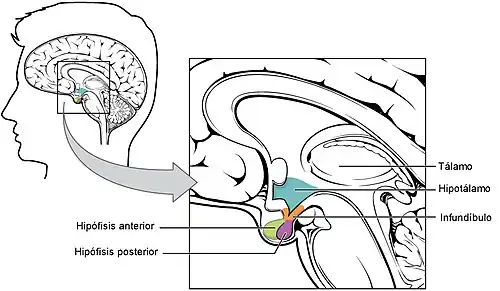

El hipotálamo[1] es una región del cerebro anterior, que forma parte del prosencéfalo secundario embrionario y en el adulto se encuentra situada debajo del tálamo.[2] Produce diferentes hormonas, entre ellas hormona antidiurética y oxitocina, también secreta varios neuropéptidos llamados factores hipotalámicos que actúan sobre la adenohipófisis y regulan su producción hormonal. Otras funciones del hipotálamo son mantener la temperatura corporal, e influir en diferentes conductas, entre ellas las relacionadas con: la alimentación, ingesta de líquidos, apareamiento y agresión. Es el regulador central de varias funciones viscerales autónomas y endocrinas y además actúa como punto de relevo en la información que partiendo del cerebro alcanza la médula espinal.[3][4]

El hipotálamo humano es el sector del encéfalo que ocupa un volumen de cuatro centímetros cúbicos, el 0.3 % del volumen encefálico normal de un adulto, y pesa entre 5-8 gramos.[5][6] Ocupa la porción más ventral del diencéfalo y forma la parte anterior de las paredes laterales y del piso del tercer ventrículo.[5] Se localiza por debajo del tálamo y es una parte importante del sistema límbico. Sus puntos de referencia externos son el quiasma óptico, el tuber cinereum y los cuerpos mamilares.[7] Está unido al lóbulo posterior de hipófisis por el tallo hipofisario o infundíbulo.[8]

En la morfogénesis, el suelo del hipotálamo forma el infundíbulo, una evaginación digitiforme y hueca, a partir de la que se desarrollan dos estructuras: la neurohipófisis y la eminencia media. Esta última es una zona de contacto neurohemático, que forma una interfaz funcional entre el hipotálamo y el lóbulo anterior de la hipófisis.[5]

Las conexiones vasculares entre hipotálamo e hipófisis se conocen como el sistema porta hipotálamo-hipófisis que comunica los lechos capilares del hipotálamo con los del lóbulo anterior de la hipófisis. La irrigación de las estructuras llega de las arterias hipofisarias superior, media e inferior, ramas de la arteria carótida interna.[10]

El hipotálamo tiene vías de comunicación de doble sentido con el sistema límbico y también envía señales eferentes en tres direcciones: posterior e inferior —hacia el tronco encefálico—, superior —hacia zonas altas de diencéfalo y telencéfalo— y hacia el infundíbulo.[6]